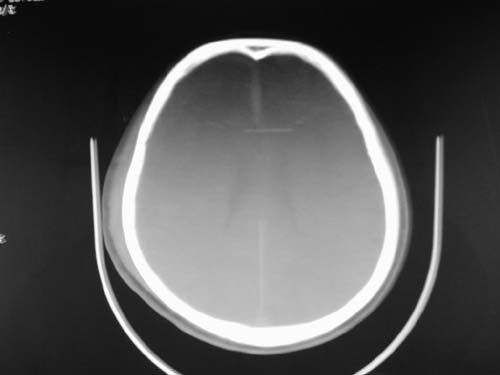

标题: CT17020:是硬膜下的吗?

脑中线内血肿,是硬膜下的吗?

脑中线内血肿——硬膜下血肿。

脑中线内血肿——硬膜下血肿。我们一般认为中线即可是硬膜下,也可是蛛网膜下腔的。边缘锐利,张力高的考虑硬膜下的,边缘模糊的,考虑下腔的。如果有老师有肯定的答案,麻烦下给我发个短信

硬膜下血肿,有颅骨骨折

支持镰旁硬膜下血肿,颅骨骨折,头皮损伤.

这个病人年龄不小吧,右侧脑沟不清,中线结构稍有左移,右侧额颞顶及右镰旁硬膜下血肿,另有蛛血,骨折。

外伤后引起的颅骨骨折、硬膜下血肿、皮下血肿,颅骨骨折引起的矢状窦破裂,形成大脑纵裂内血肿。